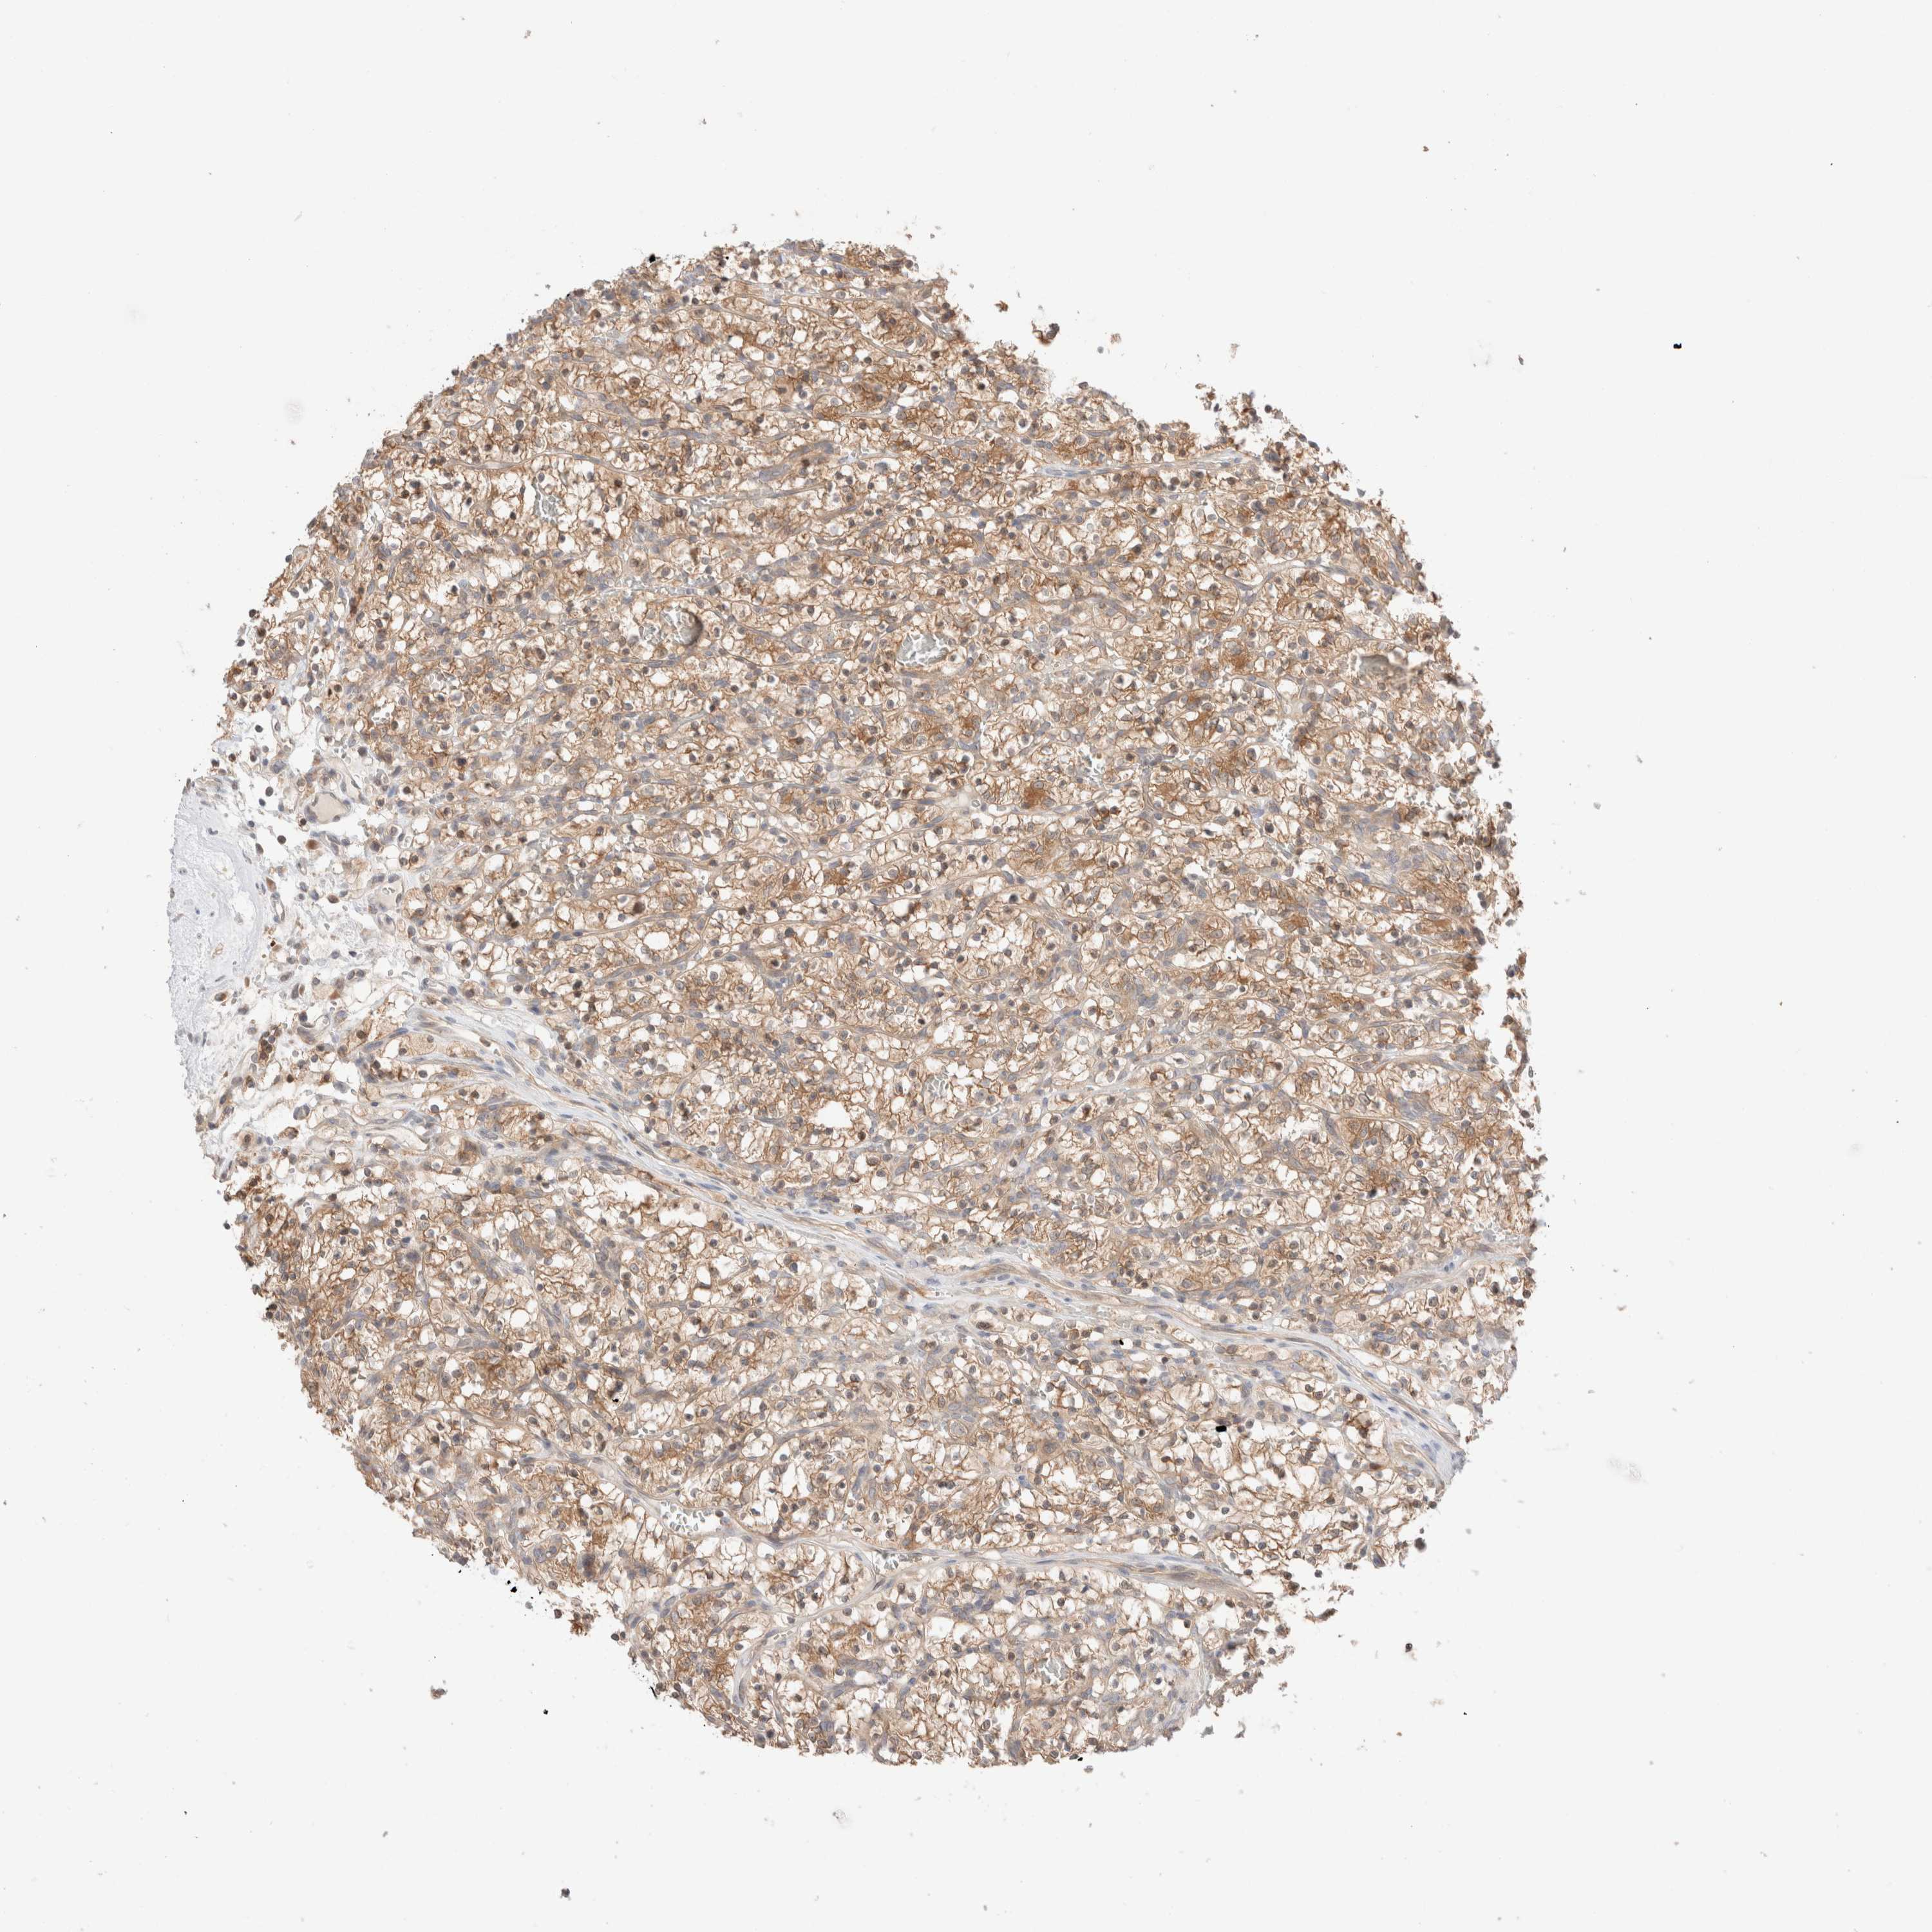

KIDNEY RENAL CLEAR CELL CARCINOMA (TCGA) - Interactive survival scatter ploti

The Survival Scatter plot shows the clinical status (i.e. dead or alive) for all individuals in the patient cohort, based on the same data that underlies the corresponding Kaplan-Meier plots. Patients that are alive at last time for follow-up are shown in blue and patients who have died during the study are shown in red.

The x-axis shows the expression levels (FPKM) of the investigated gene in the tumor tissue at the time of diagnosis. The y-axis shows the follow-up time after diagnosis (years). Both axes are complimented with kernel density curves demonstrating the data density over the axes. The top density plot shows the expression levels (FPKM) distribution among dead (red) and alive patients (blue). The right density plot shows the data density of the survived years of dead patients with high and low expression levels respectively, stratified using the cutoff indicated by the vertical dashed line through the Survival Scatter plot. This cutoff is automatically defined based on the FPKM cutoff that minimizes the p-score. The cutoff can be changed by dragging the vertical line or by entering a cutoff value in the square labeled "Current cut-off".

Under the Survival Scatter plot the p-score landscape (black curve; left axis) is shown together with dead median separation (red curve; right axis). Dead median separation is the difference in median mRNA expression between patients who have died with high and low expression, respectively. It is calculated as follows: median FPKM expression of dead patients with high expression - median FPKM expression of dead patients with low expression. This is intended to aid the user in visually exploring custom cutoffs and the associated p-scores and dead median separation.

Individual patient data is displayed and can be filtered by clicking on one or more of the category buttons on the top of the page. Categories describing expression level and patient information include: high, low, alive, dead, female, male and tumor stages. The scale of the x-axis can be toggled between linear and log-scale by clicking on the "x log" button. Mouse-over function shows TCGA ID, patient information and mRNA expression (FPKM) for each patient.

& Survival analysisi

Kaplan-Meier plots summarize results from analysis of correlation between mRNA expression level and patient survival. Patients were divided based on level of expression into one of the two groups "low" (under cut off) or "high" (over cut off). X-axis shows time for survival (years) and y-axis shows the probability of survival, where 1.0 corresponds to 100 percent.

XKR4 is not prognostic in Kidney Renal Clear Cell Carcinoma (TCGA)

TCGA RNA samplesi

RNA-seq data is reported as average FPKM (number Fragments Per Kilobase of exon per Million reads), generated by the The Cancer Genome Atlas (TCGA) .

Normal distribution across the dataset is visualized with box plots, shown as median and 25th and 75th percentiles. Points are displayed as outliers if they are above or below 1.5 times the interquartile range. FPKM values of the individual samples are presented next to the box plot.

Average pTPM 0.0

Number of samples 521